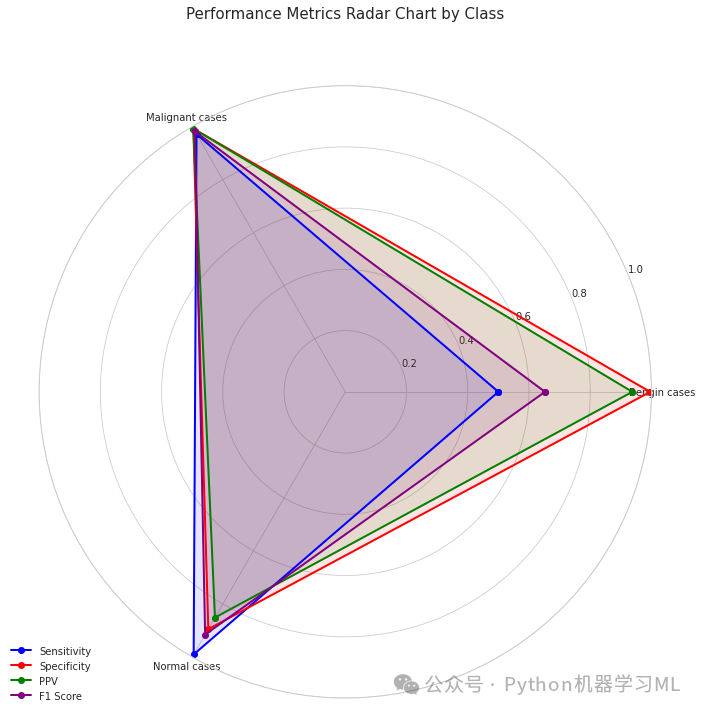

第三部分

第一阶段:雷达图可视化

这个阶段的代码实现了一个雷达图,用于展示每个类别在不同性能指标上的表现。

python# 导入医学图像可视化所需的库

import matplotlib.pyplot as plt # 导入matplotlib库,用于创建可视化图表

import seaborn as sns # 导入seaborn库,用于增强可视化效果

import numpy as np # 导入numpy库,用于数值计算

# 1. 绘制雷达图,显示模型在各种指标上的性能

defplot_radar_metrics(categories, metrics_dict):

"""

绘制雷达图,显示每个类别的多个性能指标

参数:

categories: 类别名称列表

metrics_dict: 包含指标数组/列表的字典

"""

# 设置图形

fig = plt.figure(figsize=(10, 10)) # 创建一个10x10大小的图形

ax = fig.add_subplot(111, polar=True) # 添加极坐标子图

# 打印维度用于调试

print(f"Categories: {categories}, length: {len(categories)}") # 打印类别和类别数量

for metric, values in metrics_dict.items(): # 遍历每个指标及其值

print(f"Metric '{metric}' values: {values}, length: {len(values)}") # 打印每个指标的值和长度

# 确保所有指标与类别具有相同的维度

for metric inlist(metrics_dict.keys()): # 遍历所有指标

iflen(metrics_dict[metric]) != len(categories): # 如果指标的长度与类别数量不一致

print(f"WARNING: Metric '{metric}' has {len(metrics_dict[metric])} values but there are {len(categories)} categories.") # 打印警告

print(f"Adjusting '{metric}' to match category length.") # 打印调整信息

# 选项1: 如果过长,则截断

iflen(metrics_dict[metric]) > len(categories): # 如果指标长度大于类别数量

metrics_dict[metric] = metrics_dict[metric][:len(categories)] # 截断指标使其与类别数量相同

# 选项2: 如果过短,则用零填充

eliflen(metrics_dict[metric]) < len(categories): # 如果指标长度小于类别数量

padding = np.zeros(len(categories) - len(metrics_dict[metric])) # 创建由零组成的填充数组

metrics_dict[metric] = np.concatenate([metrics_dict[metric], padding]) # 将填充数组连接到指标后

# 获取角度

angles = np.linspace(0, 2*np.pi, len(categories), endpoint=False).tolist() # 创建均匀分布的角度列表

angles += angles[:1] # 闭合图形,添加第一个角度到末尾

# 绘制每个指标

metrics = list(metrics_dict.keys()) # 获取指标名称列表

colors = ['b', 'r', 'g', 'purple'] # 设定颜色列表

for i, metric inenumerate(metrics): # 遍历每个指标

values = metrics_dict[metric].copy() # 创建指标值的副本,避免修改原始数据

values = np.append(values, values[0]) # 闭合图形,添加第一个值到末尾

# 再次检查维度

iflen(angles) != len(values): # 如果角度长度和值长度不一致

print(f"ERROR: angles has {len(angles)} elements but values has {len(values)} elements") # 打印错误信息

continue# 跳过当前指标的绘制

ax.plot(angles, values, 'o-', linewidth=2, color=colors[i % len(colors)], label=metric) # 绘制线条和标记

ax.fill(angles, values, alpha=0.1, color=colors[i % len(colors)]) # 填充区域

# 设置角度标签

ax.set_xticks(angles[:-1]) # 设置x轴刻度,不包括最后一个(闭合)角度

ax.set_xticklabels(categories) # 设置x轴刻度标签为类别名称

# 设置y轴范围

ax.set_ylim(0, 1) # 设置y轴范围从0到1

# 添加图例和标题

plt.legend(loc='upper right', bbox_to_anchor=(0.1, 0.1)) # 添加图例

plt.title('Performance Metrics Radar Chart by Class', size=15, y=1.1) # 添加标题

plt.tight_layout() # 调整布局

plt.show() # 显示图形

# 准备雷达图数据 - 明确确保所有数组具有相同的长度

categories_array = np.array(categories) # 将类别列表转换为numpy数组

n_categories = len(categories_array) # 获取类别数量

# 检查所有指标的维度

print(f"Categories shape: {categories_array.shape}") # 打印类别数组的形状

print(f"Sensitivities shape: {np.array(sensitivities).shape}") # 打印敏感度数组的形状

print(f"Specificities shape: {np.array(specificities).shape}") # 打印特异度数组的形状

print(f"PPVs shape: {np.array(ppvs).shape}") # 打印PPV数组的形状

print(f"F1 scores shape: {np.array(class_f1).shape}") # 打印F1分数数组的形状

# 确保所有指标具有正确的维度

sensitivities_array = np.array(sensitivities) # 将敏感度列表转换为numpy数组

specificities_array = np.array(specificities) # 将特异度列表转换为numpy数组

ppvs_array = np.array(ppvs) # 将PPV列表转换为numpy数组

f1_array = np.array(class_f1) # 将F1分数列表转换为numpy数组

# 如果需要,截断或填充

iflen(sensitivities_array) != n_categories: # 如果敏感度数组长度与类别数量不一致

sensitivities_array = np.resize(sensitivities_array, n_categories) # 调整敏感度数组大小

iflen(specificities_array) != n_categories: # 如果特异度数组长度与类别数量不一致

specificities_array = np.resize(specificities_array, n_categories) # 调整特异度数组大小

iflen(ppvs_array) != n_categories: # 如果PPV数组长度与类别数量不一致

ppvs_array = np.resize(ppvs_array, n_categories) # 调整PPV数组大小

iflen(f1_array) != n_categories: # 如果F1分数数组长度与类别数量不一致

f1_array = np.resize(f1_array, n_categories) # 调整F1分数数组大小

# 使用校正后的数组创建指标字典

radar_metrics = {

'Sensitivity': sensitivities_array, # 敏感度

'Specificity': specificities_array, # 特异度

'PPV': ppvs_array, # 阳性预测值

'F1 Score': f1_array # F1分数

}

# 使用校正后的数据调用函数

plot_radar_metrics(categories, radar_metrics) # 调用雷达图绘制函数